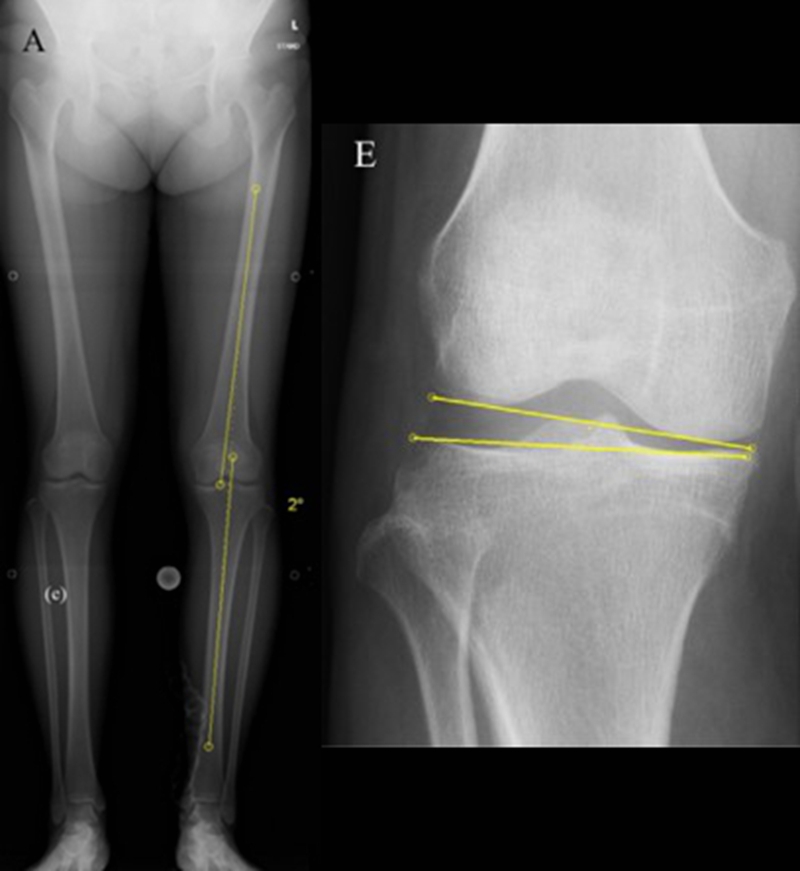

关于SONK与下肢力线的关系,一项研究结果显示SONK组MPTA畸形比OA组更大,高达约1.5°,SONK组JLCA也显著高于OA组。

提示胫骨近端内翻畸形和膝关节松弛,有助于诱发SONK,SONK骨软骨病变的大小受胫骨近端内翻畸形的影响。临床中MPTA小于 84°且伴有急性膝关节疼痛应尽快MRI检查。

膝内翻 内侧半月板根部撕裂

病例1:女,65岁,主诉右膝关节内侧疼痛1周。2018年1月X光未见右膝骨质异常,MR检查见股骨内侧髁骨坏死,半月板相对突出百分比(RPE)28.99%,关节线会聚角1.4°。

病例2:女,69岁,主诉左膝关节内侧疼痛1月余。2017年11月X光见右膝股骨髁负重区的软骨下区域出现了椭圆形透亮影,MR检查见股骨内侧髁骨坏死,合并内侧半月板外突和后角层裂,半月板相对突出百分比(RPE)25.32%,矢状位病变区域前后径为23.96mm,关节线会聚角6°。

已经累及44%的股骨内侧髁病变,半月板轻度突出,内侧后角水平撕裂

MRI上深度>20mm